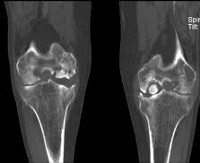

Болезнь Кёнинга или рассекающий остеохондрит

Болезнь Кёнинга

Данное заболевание характеризуется отслоением хрящевой ткани от кости и даже полным ее отделением. При этом тканевой фрагмент свободно перемещается в полости сустава, препятствуя движению и вызывая болезненные ощущения.

Одним из основных предрасполагающих факторов считается нарушение кровообращения в поврежденном участке. Отторжение хряща занимает длительное время, поэтому связь с предшествующей травмой удается установить крайне редко.

В зависимости от степени тяжести состояния выделяют несколько стадий заболевания:

- Размягчение хрящевой ткани, «выпячивание» поврежденной ткани в суставную полость.

- Прогрессирование симптомов, появление первых признаков заболевания на рентгенограмме.

- В области поражения появляется асептическое расплавление тканей, может возникать частичное отторжение хряща.

- Некротизированная ткань полностью отделяется от кости и свободно «дрейфует» в полости сустава.

Как и любая остеохондропатия, болезнь Кёнинга развивается медленно и симптоматика нарастает постепенно. Первые проявления — это болезненные ощущения во время движения и в покое. Затем нарастает отек коленного сустава и нарушается его функция за счет скопления большого количества внутрисуставной жидкости (из-за воспалительно-дегенеративного процесса).

При четвертой стадии (отделение некротизированной ткани) возможно блокирование сустава. Причиной этого становится так называемая «суставная мышь», которая вклинивается между суставными поверхностями. Она же может стать причиной развития деформирующего артроза.

Рассекающий остеохондрит или болезнь Кенига. Асептический некроз, вследствие которого небольшой участок хряща отделяется от подлежащей кости и смещается в полость сустава, образуя свободно лежащее внутрисуставное тело. В основном страдает мыщелок бедренной кости, хотя возможно также поражение лучезапястного, локтевого, тазобедренного и голеностопного сустава. В редких случаях выявляется рассекающий остеохондрит надколенника и большеберцовой кости. Заболевание проявляется незначительными болями в суставе. Со временем боли усиливаются. После формирования суставной мыши возникают блокады, замыкание и похрустывание в пораженном суставе. На начальных стадиях у детей достаточно эффективно консервативное лечение. После отделения участка хряща необходима операция. У детей и подростков прогноз благоприятный. Если болезнь возникла в более зрелом возрасте, существует риск развития остеоартроза.

В норме суставные поверхности костей покрыты плотным, упругим и гладким гиалиновым хрящом. Это позволяет костям беспрепятственно скользить друг относительно друга при движениях. При рассекающем остеохондрите в небольшом сосуде, питающем участок кости, возникает тромбоз. Питание расположенного над этим участком хряща нарушается, формируется зона асептического некроза.

Со временем некротизированный хрящ отслаивается и попадает в сустав, образуя «суставную мышь» — свободно лежащее внутрисуставное тело, которое перемещается по суставу и, попадая между поверхностями костей при движениях, может вызывать блокады. Поврежденный участок теряет свою гладкость, становясь причиной перегрузок и дальнейшей травматизации сустава. В результате может развиться остеоартроз.

Выделяют четыре стадии заболевания:

• 1 стадия. Дискомфорт и неясные незначительные боли без четкой локализации. На рентгенограмме выявляется овальное некротизированное тело, отделенное полоской просветления от здоровой кости.

• 2 стадия. Умеренные боли в суставе, явления синовита. Полоса просветления на рентгеновских снимках становится шире. Целостность замыкательной пластинки на поврежденном участке нарушается.

• 3 стадия. Боли, похрустывание и «заедание» сустава. Возможны блокады. На рентгенограммах выявляется некротизированный участок, частично отделившийся от кости.

• 4 стадия. Боли усиливаются, однако блокады становятся более редкими. Отмечается нарастание синовита. На рентгеновских снимках обнаруживается полностью отделившееся внутрисуставное тело.